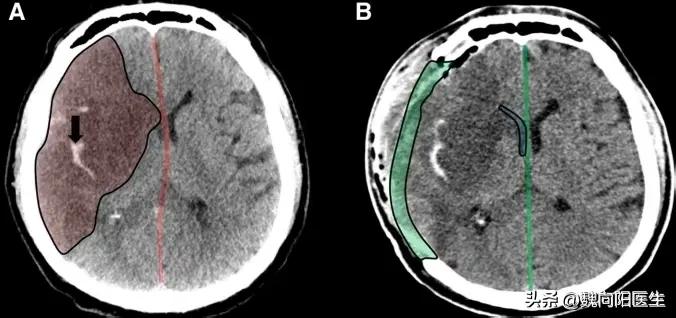

锯掉头骨的目的

为了减轻恶性脑水肿对于正常脑组织压迫及颅内压增高的症状,对于出现脑疝的患者,及时的纠正脑疝症状。医生往往需要把患者的头盖骨去掉,让多余的压力向外充分释放,从而保护正常的脑组织,降低颅内压。

总之医生锯掉患者的头开骨就是为了降低颅内的压力,待患者脑水肿消退后,保住患者的性命,尽可能的减少正常脑组织的继发性损害,待病情稳定之后,择期行颅骨修补术。